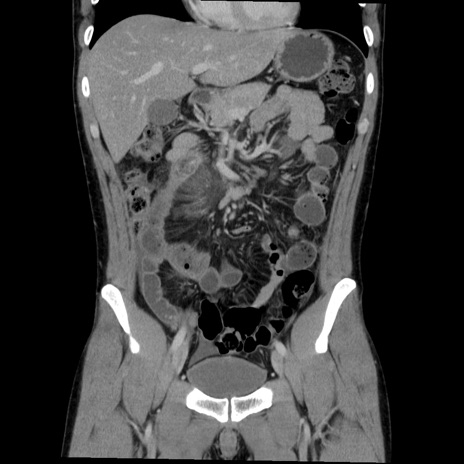

症例36(冠状断像)

【症例】20歳代 男性

【主訴】心窩部痛

【現病歴】今朝より上腹部痛あり。一旦軽快していたが再度出現したため救急要請。昨日夕に白身の魚を含む刺身を食べた。

【身体所見】BP 136/89mmHg、HR 74/min、BT 37.0℃、腹部:膨満、軟、心窩部に圧痛あり。反跳痛なし、筋性防御なし、腸雑音やや亢進あり。

【データ】WBC 17700、CRP 0.48